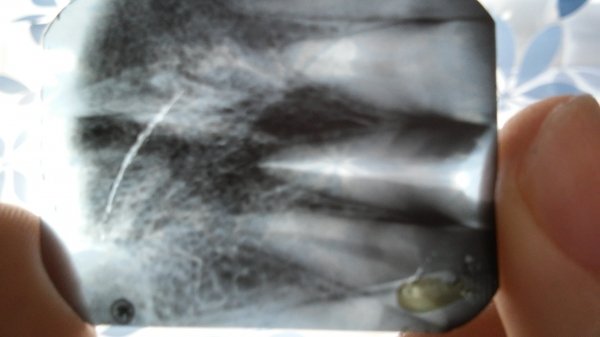

Добрый день. Хотелось узнать про передний зуб. Удаляли нерв года 3 назад, но практически все время реагирует на горячее и холодное и тд. А в апреле сильно опухла десна. Сейчас была у стоматолога сделали снимок сказали, что киста. Подскажите хирургическим ли методом ее надо удалять. Заранее спасибо.

Добрый день, уважаемая Наталья! Судя по снимку, мы имеем очень большую резекцию костной ткани вокруг этого зуба. Эндодонтическим методом такого рода кисту уже вряд ли можно вылечить. Да и резекция судя по снимку не спасет зуб. Я имею ввиду то, что кости и так мало и после резекции, а она подразумевает отсечение инфицированного корня, в кости останется 2-3 мм корня, что недопустимо и достаточной фиксации зуба в кости не будет. Возможно на снимке наложение и мы ошибаемся, поэтому настоятельно рекомендую приехать ко мне на осмотр для принятия решения. Всего вам доброго!